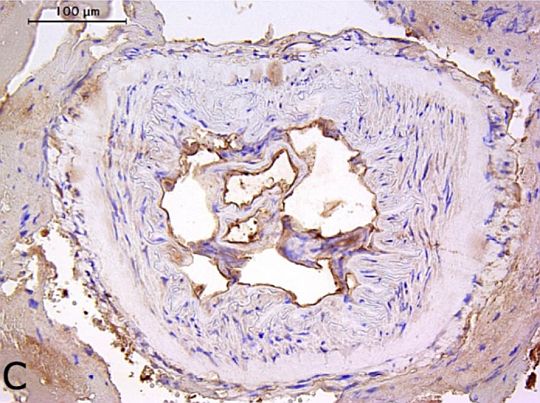

A beoltott betegek 43,8 %-ánál kimutatható volt a tüskefehérje expressziója, túlnyomórészt az agyi artériák belső rétegében, egy esetben még 17 hónappal az oltás után is. Egyik esetben sem volt jelen aktív vírusfertőzés, ami onnan tudható, hogy nem volt kimutatható az ilyen fertőzés egyik jellemzője, a nukleokapszid fehérje.

Bár nem zárható ki teljesen a tünetmentes SARS-CoV-2 fertőzés okozta tüskefehérje-expresszió lehetősége, ez a vizsgálat kimutatta a SARS-CoV-2 tüskefehérje elhúzódó jelenlétét az agyi artériákban az mRNS-oltást követően. Emellett a tüskefehérje-pozitív erekben gyulladásos sejtek bizonyos mértékű beszivárgása volt megfigyelhető. Ezek az eredmények jelentős aggodalomra adnak okot a lipid nanorészecske-alapú oltások biodisztribúciójával és hosszú távú biztonságosságával kapcsolatban. Sürgősen szükség van globális replikációs vizsgálatokra ezen eredmények megerősítése és az mRNS-oltások átfogó biztonsági értékelésének biztosítása érdekében.